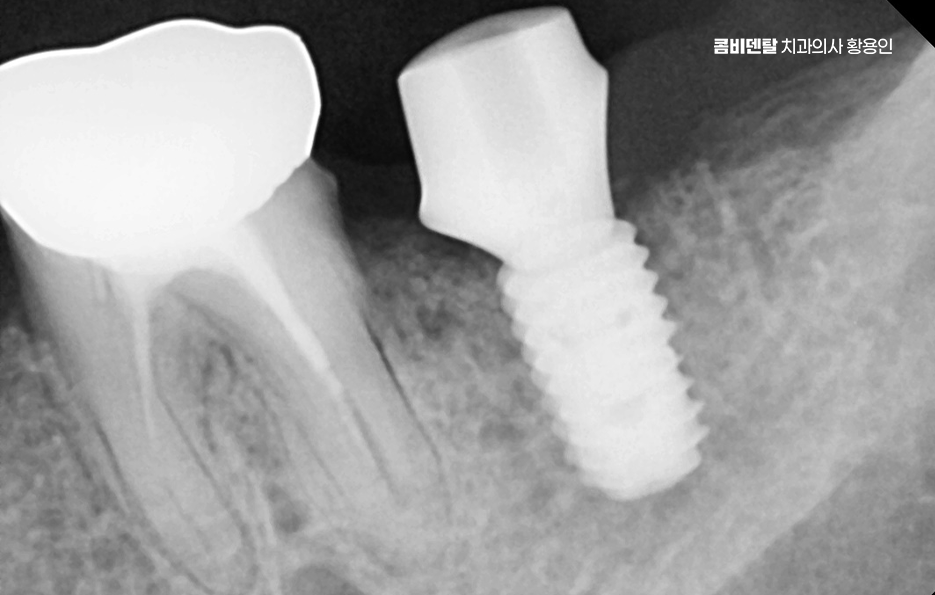

치아 발치 후 임플란트 치료 과정을 살펴보면 임플란트는 티타늄이라는 재료로 만든 인공 치근을 잇몸 뼈에 식립하고, 그 위에 보철물을 올리는 구조로 티타늄은 인체에 잘 맞는 재료라 뼈와 자연스럽게 붙는 성질이 있는데 이 과정을 ‘골융합’이라고 하고 이 골융합이 안정적으로 일어나야만 임플란트가 오래 버틸 수 있고, 자연치아처럼 역할을 할 수 있는 거예요.

치아 발치 후 임플란트 치료 과정은 처음에 CT나 파노라마 엑스레이를 통해 뼈의 양과 밀도, 신경 위치를 정확히 확인하는 것부터 시작되며 치아가 빠진 자리에 뼈가 많이 흡수되어 있다면, 임플란트를 심기 전에 뼈이식을 먼저 해야 할 수 있지만 반대로 뼈 상태가 좋다면 임플란트를 심고, 보통 3개월 동안 뼈와 잘 붙을 때까지 골융합 과정을 기다리게 되며 골융합이 잘 이루어진 뒤에는 그 위에 지대주라는 연결 부품을 끼우고, 그 위에 최종 보철물을 씌우면서 치료가 마무리되고 있어요